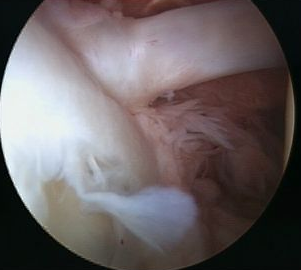

Arthroscopy

Normal insertion of superior labrum onto glenoid

Snyder Arthroscopic Classification SLAP tears

|

Superior labrum frayed Labrum and biceps anchor intact |

Superior labrum and biceps anchor torn off glenoid |

Bucket handle tear of superior labrum Biceps anchor intact |

Bucket handle tear of superior labrum and biceps tendon |